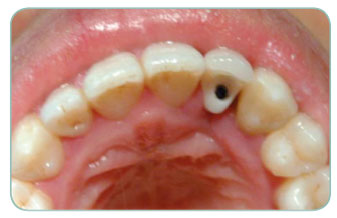

On the back of a trauma our patient had lost his up front teeth. We have applied one Implant together with a zirconium porcelain.